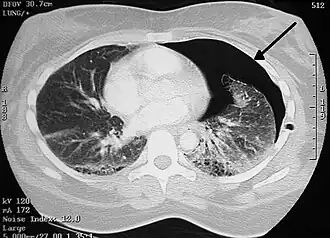

Le scanner thoracique permet de faire le bilan des blebs et des bulles des 2 poumons, de dépister une éventuelle tumeur pulmonaire et de connaître l’état du poumon sous-jacent.